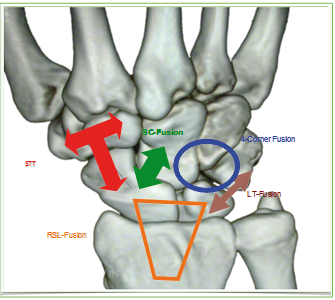

Eine der ersten Teilarthrodesen war die mediokarpale Teilarthrodese, wie von Watson 1981 beschrieben. Hierbei handelte es sich um die Fusion des Capitatums, Hamatums, Triquetrums und Lunatums, das Kahnbein muss entfernt werden. Eine ebenfalls schon lange bestehende Methode ist die STT-Arthrodese. Diese wird verwendet um z. B. bei einem schleichenden Mondbeintod durch eine Versteifung des STT-Gelenks den Erhalt der karpalen Höhe zu erreichen, und ein Zusammensintern des gesamten Carpus zu vermeiden.

Nachteil dieser Methode ist jedoch die Entstehung einer Transferarthrose, d. h. eine Arthrose, die sich dann aufgrund der veränderten Kinematik auf das radioscaphoidale Gelenk erstreckt. Ein großes Problem stellten lange Zeit die Arthrosen des radiocarpalen Gelenkspaltes z. B. nach Radiusfrakturen dar. Die RSL-Fusion bietet hier einen Ausweg. Dabei werden das Kahnbein, das Mondbein und der Radius verblockt und es verbleibt eine Restbeweglichkeit im mediokarpalen Gelenkspalt. Der distale Kahnbeinpol sollte reseziert werden um das Bewegungsausmaß zu erweitern.

Bei der rheumatischen Erkrankung mit Ulnashift des gesamten Handgelenkes kommt seit Jahren die RL-Fusion zum Tragen. Hierbei wird das Mondbein in seine ursprüngliche Lage zurücktransponiert und dann mit Schrauben oder Drähten gehalten, um so eine Fusion zu erzielen. Diese Methode kann die fortschreitende Arthrose des Handgelenkes durchaus herauszögern. Speziell bei der RL-Fusion sollte jedoch dieser Eingriff frühzeitig erwogen werden, da bei einem zu starken Ulnashift die Handwurzel schon so stark verblockt sein kann, dass eine Reposition kaum noch möglich ist.

Wesentlich seltenere Arthrodesen im Bereich des Handgelenkes sind die ST- und die LT-Fusionen mit häufigen Pseudarthrosen und die CMC-Fusionen. Insgesamt ist bei den gesamten Fusionen des Carpus zu berücksichtigen, dass ein Aufrichten des Carpus oftmals nur sehr schwer möglich ist. Über die Erhaltung der karpalen Höhe wird kontrovers diskutiert. Hier wird auf der einen Seite die Verwendung von kortikospongiösen Spänen zum Erhalt der karpalen Höhe beschrieben. Auf der anderen Seite verzichtet man in den letzten Jahren immer häufiger auf die Wiederherstellung der karpalen Höhe, um somit Beckenkammspäne zu vermeiden. Als Begründung für die Nichtbeachtung der karpalen Höhe wird hier immer die proximale Row-Carpektomie angegeben. Eine Methode, bei der die gesamte proximale karpale Reihe reseziert wird. Hierbei wird die karpale Höhe massiv verringert, ohne eine wesentliche Einschränkung der Funktion zu verursachen.